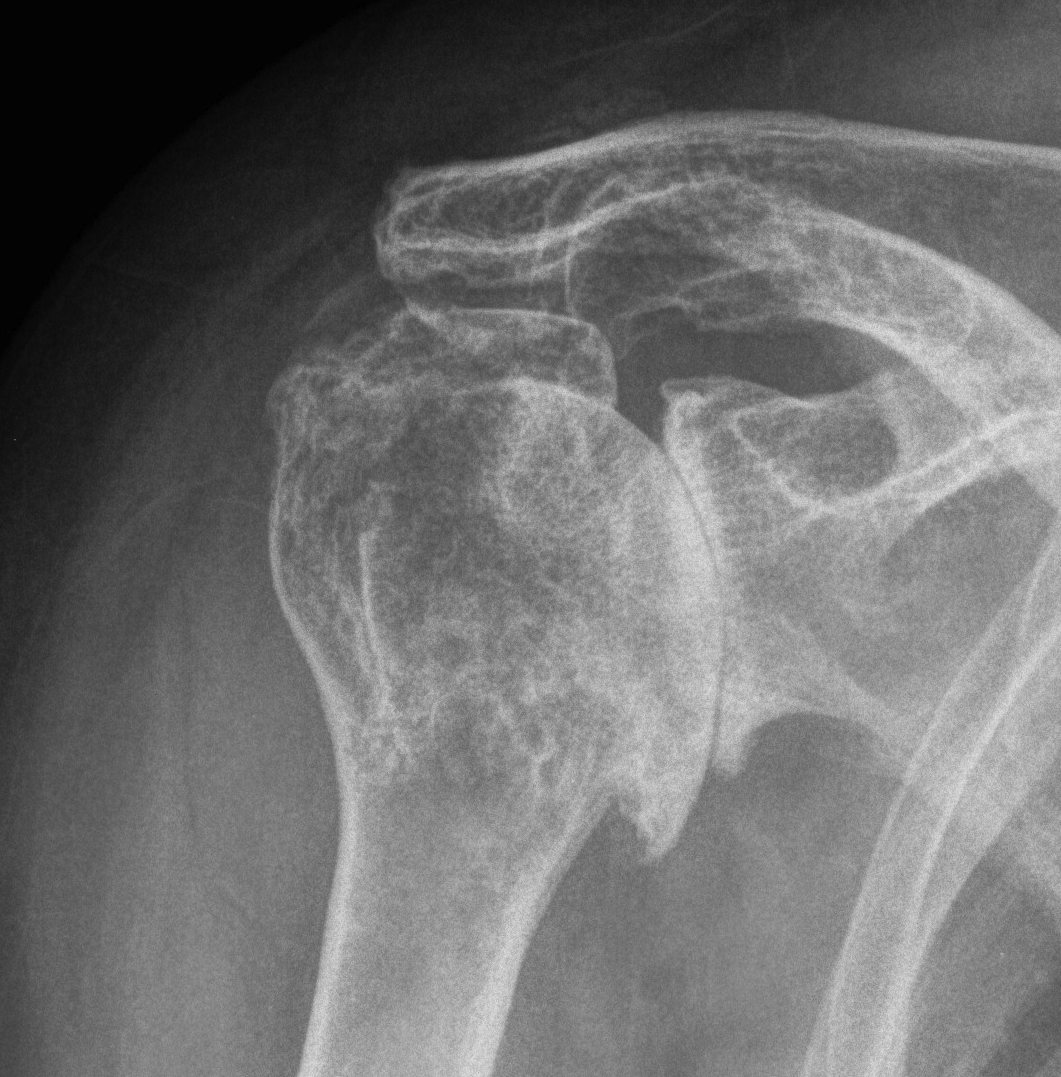

proximal humerus fracture Background ORIF with locking plate Arthroplasty Greater tuberosity fractures Lesser tuberosity fractures / avulsions Book traversal links for Proximal humerus fractures ‹ Pectoralis Major Tears Up Background ›